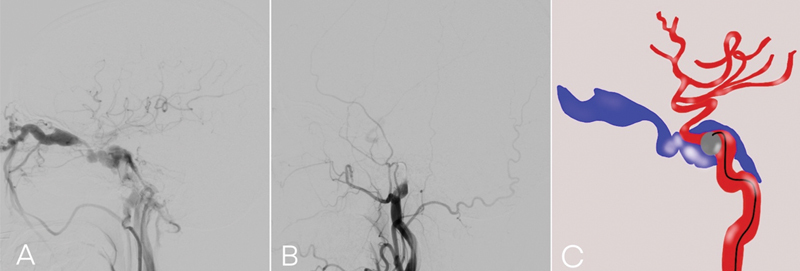

Objectives  This article evaluates the outcomes and efficacy of detachable balloon embolization by single balloon delivery catheter, while identifying factors associated with successful embolization in traumatic carotid cavernous fistula (TCCF) patients. Materials and Methods  We retrospectively collected data of TCCF patients who underwent detachable balloon embolization during March 2020 to April 2024. All cases utilized a single balloon delivery catheter for detachable balloon deployment (GOLDBAL, BALT Extrusion, France). We analyzed demographic, clinical, imaging, and angiographic data, including outcomes, complications, and factors associated with successful embolization. Results  Thirty patients were treated with detachable balloon embolization. The mean age of the patients was 41.1 years (range 17-65 years). The median duration of symptom was 2.0 months (range 0.25-60 months). The most common mechanism of injury is motorcycle accident (83.3%). Nearly all patients had eye redness and proptosis. Angiographic data indicated 29 patients (96.7%) had drainage to the inferior petrosal sinus, 28 (93.3%) had drainage to the superior ophthalmic vein, and 8 (26.7%) had drainage to the superior petrosal sinus. Five cases (16.7%) were classified as small-sized fistula, 19 (63.3%) as medium-sized, and 6 (20%) as large-sized. Regarding the location of the fistula, 8 cases (26.7%) were found in the horizontal segment, while 22 cases (73.3%) were located in the ascending or genu segment of the cavernous internal carotid artery (ICA). Among the 24 patients (80%) who underwent successful embolization, the ICA was preserved in 23 out of 24 patients (95.8%). The remaining patient had ICA occlusion but exhibited no clinical symptoms. Residual cavernous aneurysm was found in two patients, one patient had persistent cranial nerve deficit, while the other was asymptomatic. Statistical analysis demonstrated a significant difference was associated with the fistula location at the ascending or genu segment of the cavernous ICA in relation to successful embolization Conclusion  Despite the availability of several endovascular treatment options for TCCF, using detachable balloon embolization is a relatively straightforward procedure. When combined with a thorough understanding of cavernous sinus anatomy, this approach can significantly enhance the occlusion rate and preserve ICA patency while minimizing complications, particularly when the fistula is located at the ascending or genu segment of the cavernous ICA.